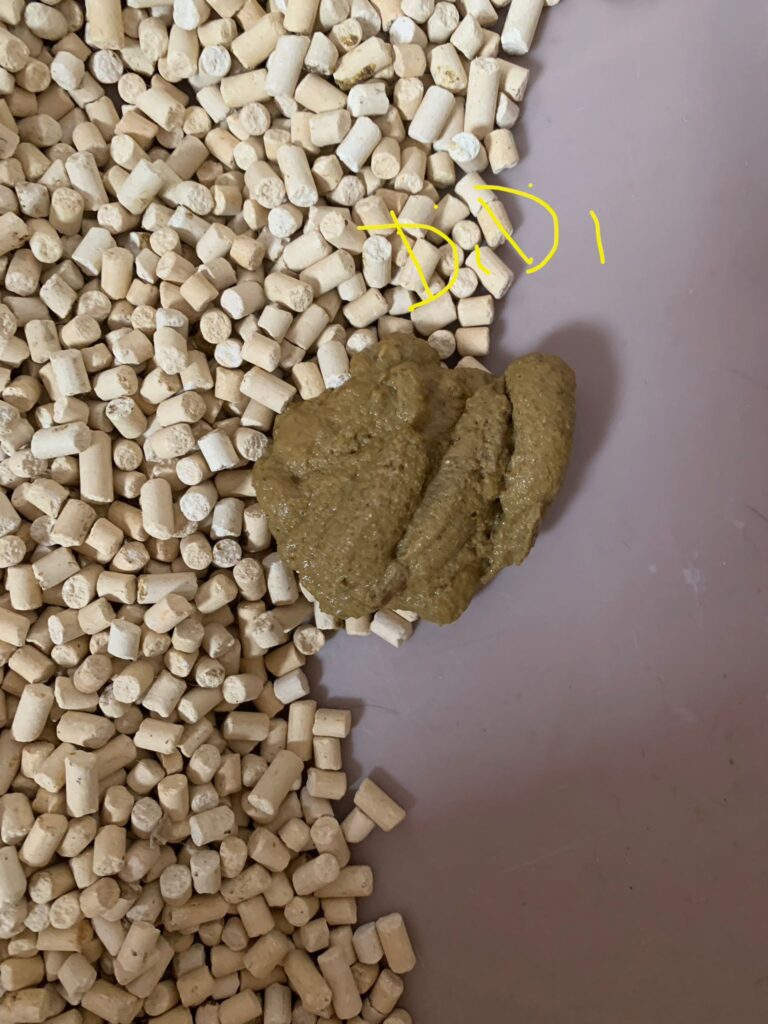

1pm: poo 4.5/10

Morning: didi constipated, saw him in 2 bins, trying to squeeze out something n can’t n he try to rub on floor – aren’t that pushing that piece in? I help him push out the 2cm piece 5/10, and he go to bin 03 and poo out another 12cm. So is that piece stuck n he is so uncomfortable. Subcut him w bupre also. His f patch still on. Can tear off soon. Need to buy more

Morning: sometime he will meow n meow at me. Want me sayang? In pain? Want some snacks? I sayang, f patch still on. I give him kelly n co fish don’t want, some Korean ciao like treat don’t want, given pidan prawn also don’t want. Have to think of what to bring over for him. Poo 4.5/10

Night: poo long n firm 5/10

7am+: he poo 1.5/10 w tinted blood. Reaction to niramine?

Night: poo 5/10, poo when i about to leave. Erm. Nice formed not much smell

He poo 1.5/10, w blood (dr d says may be due to stress)

Poo 2/10 paste, given probiotics

1pm+: poo 2.5/10, give probiotics and nutriplus gel. Given Subcut w b12 bcom.

He poo again 2.25/10.

Morning: poo like ice cream cone texture, small smelly!!